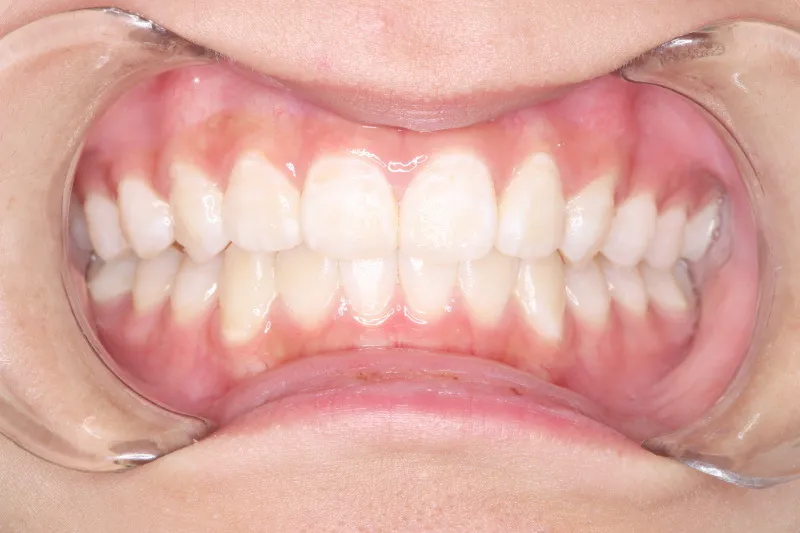

• 治療終了後

治療終了後

治療回数43回、7年4ヶ月の治療期間で矯正治療を終了しました。

主訴が改善され、ご満足頂きました。